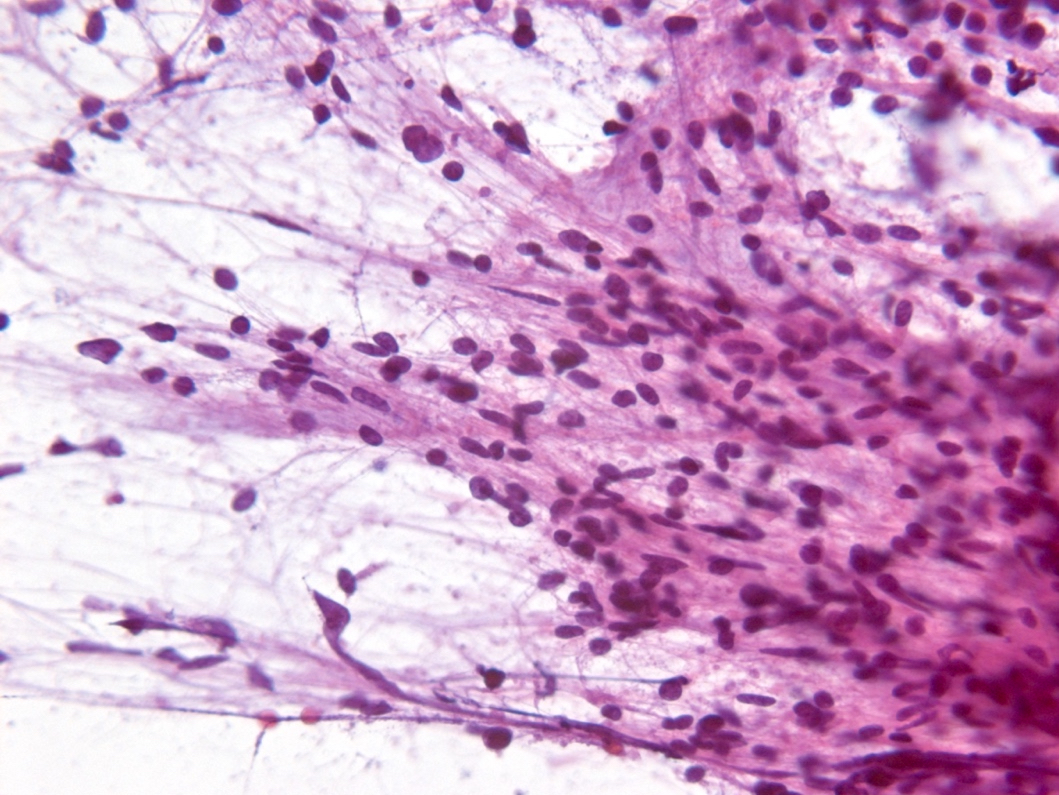

Frozen section description

- Smear done at the time of frozen section will show astrocytic appearing tumor cells with oblong irregular nuclei with varying degrees of atypia and glial processes

- High grade nuclear features and mitotic activity may be observed on frozen section but necrosis or microvascular proliferation (features of glioblastoma) should not be present

- Cellular morphology can be highly variable

- Often predominantly tumor cells with oval hyperchromatic nuclei in a fibrillary background

- Variably present, larger cells and pleomorphism

- Variable quantity of cells with eccentric nuclei and glassy eosinophilic cytoplasm (gemistocytes)

- Some show predominantly small cells with little pleomorphism and scant cytoplasm

- Sections are hypercellular showing infiltrating neoplastic cells with edema

- Variably present mitotic figures, necrosis and microvascular proliferation

- Vascular thromboses and myxoid background may be present

- Smear most commonly shows predominantly smaller cells with fine fibrillar processes, elongated nuclei, nuclear atypia and may show mitotic figures

Intraoperative frozen / smear cytology images